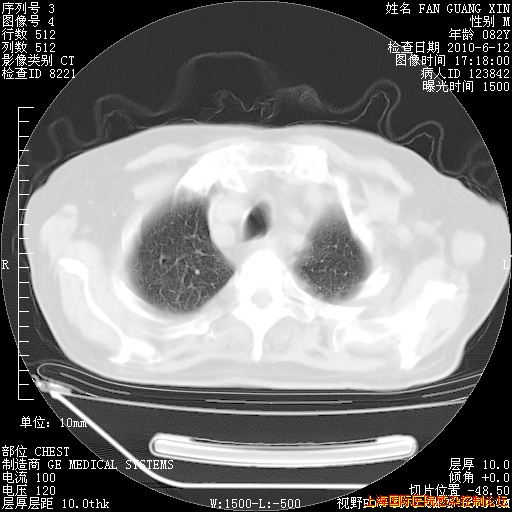

补发6月12日肺部CT肺窗

6月12日肺窗